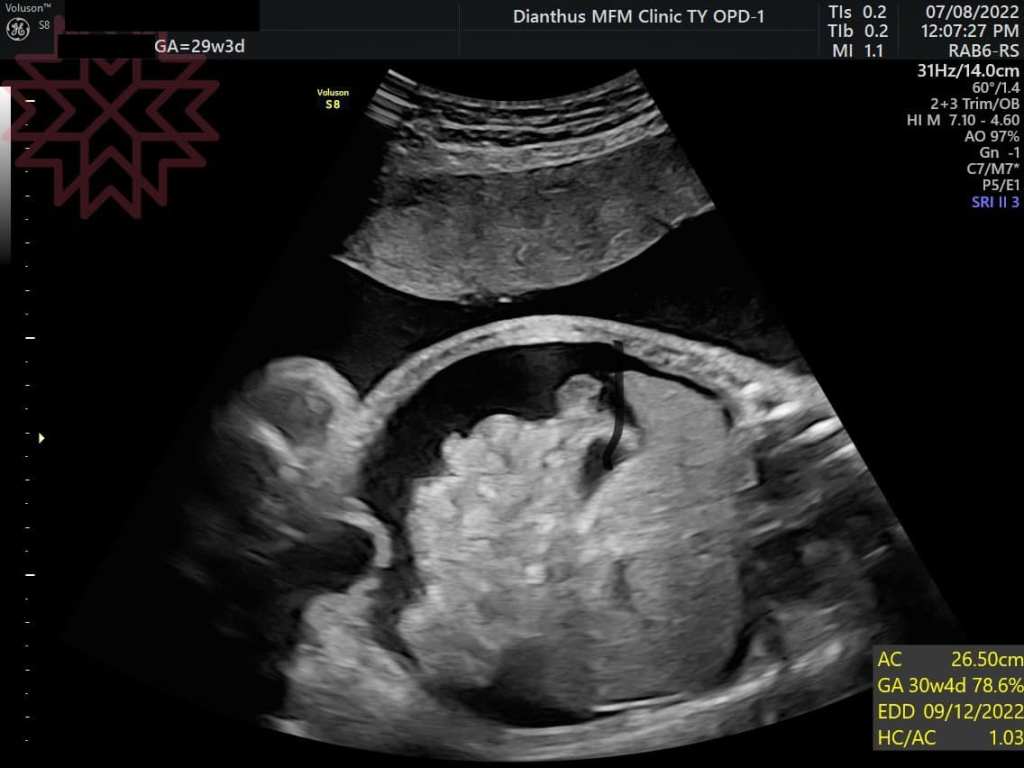

甚至到29週的時候

寶寶的心臟不堪負荷產生心臟衰竭

開始有腹水及胎兒水腫的狀態(如圖)(細節就不說了)